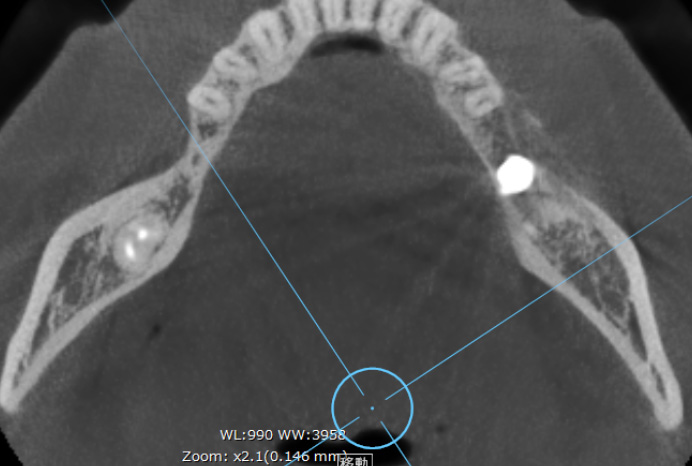

インプラント周囲の骨量を

確保した設計例

CT(アキシャル像)で確認すると、天然歯と比べて、インプラント周囲には計画的に骨量を確保していることが分かります。

これは周囲炎リスクを下げるために、埋入ポジションと骨のバリアを意識して設計しているためです。

※症例により条件は異なります。